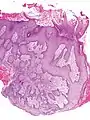

- Pseudoepitheliomatous hyperplasia (PEH) is a benign condition characterized by hyperplasia of the epidermis and epithelium of skin appendages,[32] with irregular squamous strands extending down into the dermis,[33] and closely simulating squamous cell carcinoma (SCC).[32]

Pseudoepitheliomatous hyperplasia (PEH), low magnification, with acanthotic squamous epithelium with irregular thick finger-like downgrowths into the underlying dermis.